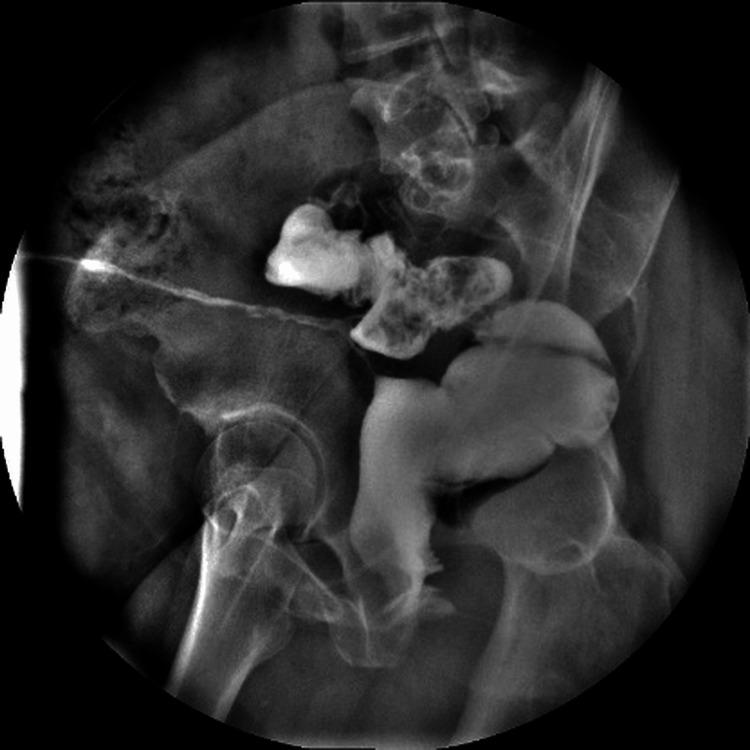

Colocutaneous fistulas are a rare but challenging complication of abdominal and pelvic surgery. Their surgical management can be difficult, especially when associated with multiple failed treatments. Transanal minimally invasive surgery (TAMIS), initially designed for local excision of rectal tumors, has been increasingly used in complex benign conditions. We present the case of a 41-year-old female patient with a chronic rectocutaneous fistula that developed following a hysterectomy and had persisted despite four failed endoscopic clip placements. The patient also reported intermittent passage of air through the vagina; however, no rectovaginal communication was identified through imaging, endoscopy, or intraoperative exploration. The fistula orifice was located 15-16 cm from the anal verge and was approached using a TAMIS platform, allowing for direct endoluminal access and precise intracorporeal suturing. The procedure lasted 65 minutes, with minimal blood loss. The patient had an uneventful recovery and was discharged 48 hours later. Long-term follow-up at three years demonstrated complete and durable resolution of the fistula, without recurrence or complications. This case illustrates the utility of TAMIS in the definitive management of complex post-hysterectomy rectal fistulas and supports its use as a safe and effective alternative to more invasive procedures in selected non-oncologic cases.

结肠皮肤瘘是腹部和盆腔手术中一种罕见但具有挑战性的并发症。其手术治疗可能很困难,尤其是在与多次治疗失败相关时。经肛门微创手术(TAMIS)最初设计用于直肠肿瘤的局部切除,越来越多地用于复杂的良性疾病。我们报告了一例41岁女性患者,她在子宫切除术后出现慢性直肠皮肤瘘,尽管进行了四次内镜夹闭术均失败,但瘘仍持续存在。患者还报告有气体间歇性经阴道排出;然而,通过影像学、内镜检查或术中探查均未发现直肠阴道瘘。瘘口距肛缘15 - 16厘米,使用TAMIS平台进行处理,可实现直接腔内入路和精确的体内缝合。手术持续65分钟,失血极少。患者恢复顺利,48小时后出院。三年的长期随访显示瘘完全持久愈合,无复发或并发症。该病例说明了TAMIS在子宫切除术后复杂直肠瘘的确定性治疗中的实用性,并支持其作为选定非肿瘤病例中更具侵入性手术的安全有效替代方法。